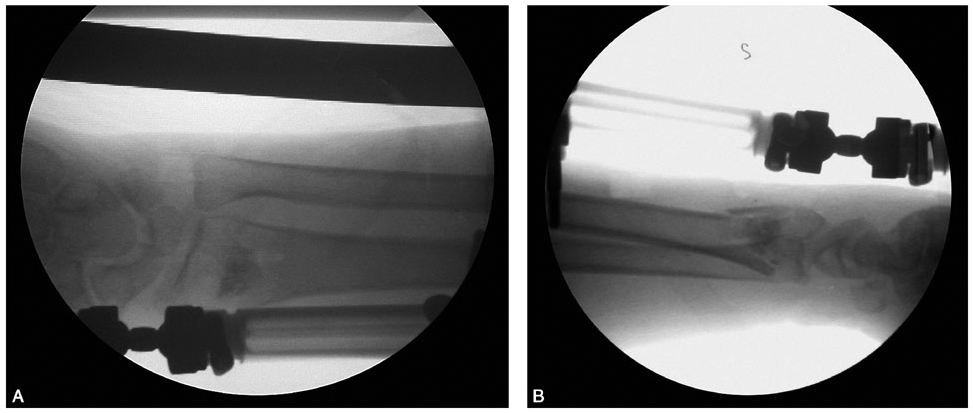

术前拍腕关节正、侧位X线片,腕关节冠状位、矢状位和水平位CT(图2-2)。此患者骨缺损和无法闭合复位的骨片均在背侧,宜采用背侧入路,复位,植骨,固定。取患肢前臂远端桡背侧纵切口(图2-3),从伸拇长肌腱和桡侧伸腕长、短肌之间进入,注意保护血管神经和肌腱,显露清理折端骨缺损区域和背侧移位的骨片(图2-4),复位,植骨,外固定架超关节固定(图2-5、图2-6)。术中透视骨折复位固定满意(图2-7),术后拍X线片证实(图2-8)。此手术的优点在于避免了局部存在内固定物的刺激,避免二期切开取出固定物所致的再次损伤。

图2-3 切口起自桡骨茎突,向上沿桡骨后缘并略偏向尺侧

图2-4 显露桡骨远端背侧骨缺损区和移位的骨片

图2-5 外固定架超关节固定

图2-6 显示植骨和骨片复位

图2-7 术中透视示骨折复位、固定、植骨满意